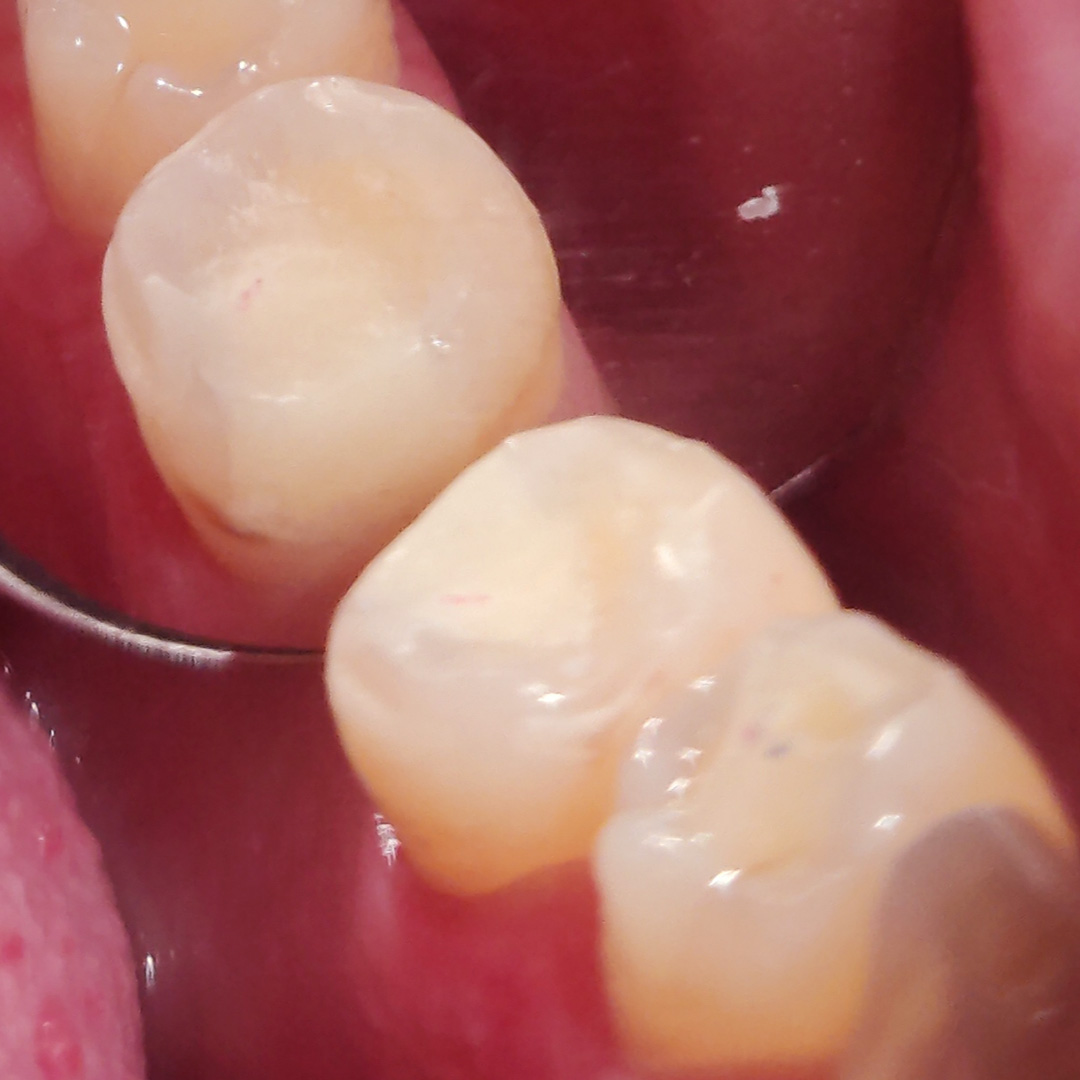

К нам в клинику обратился пациент с жалобами на эстетический недостаток в нижнем зубе слева. Отметил кратковременные быстропроходящие боли от химических раздражителей. После обработки полости под контролем кариес маркера был выявлен глубокий кариес, дно и стенки полости плотные. Наблюдалась незначительная и быстропроходящая реакция на холод. Доктор Григорьев Пётр Игоревич поставил диагноз: хронический глубокий кариес 3.5 зуба. Затем был составлен и утверждён план лечения.

В ходе лечения были проведены следующие работы:

- с использованием системы OptaGate проведена механическая обработка кариозной полости

- медикаментозная обработка с использованием Хлоргексидина 2%

- поставлена пломба Vitremer A3 с использованием матричной системы Тофельмаера

- проведено микроконтурирование и макроконтурирование пломбы.